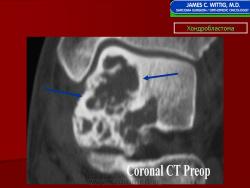

Рентгенологически хондробластома представляет собой сравнительно большой (2-4 см) очаг округлой формы, четко отграниченный от окружающей кости склеротической каймой. На фоне очага в большинстве случаев, но не обязательно определяются плотные включения, напоминающие хлопья ваты.

Рентгенологическая картина. Хондробластома выглядит как небольшой, от 3 до 6 см литический очаг, центрально или эксцентрично расположенный, с четкими контурами, занимающий около половины площади эпифизарной зоны. Хондробластома плоских костей и мелких трубчатых костей больших размеров, может сопровождаться припухлостью мягких тканей, вздутием кости и периостальной реакцией. Распространение процесса на метафизарную зону встречается часто.